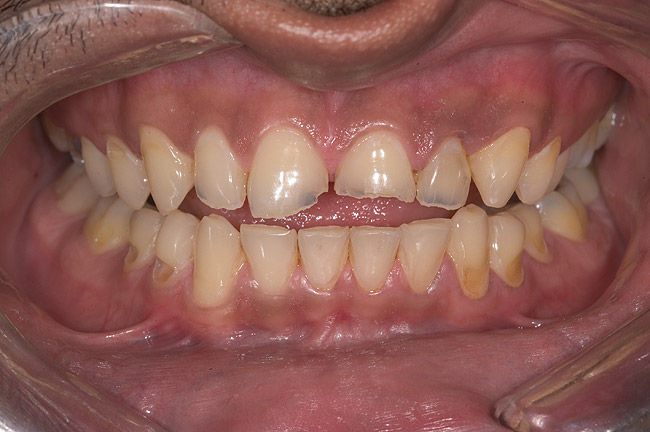

A 20-year-old male patient presented with irregular upper anterior teeth and was unhappy with his smile (Figure 4). He complained of occasional generalized mild sensitivity. Dental treatment history revealed that he had occasional dental work done in the past. Two weeks previously, he had severe pain in tooth No. 10, which was treated endodontically, and he was then referred to the author’s practice for management of anterior wear. Tooth No. 3 had a broken amalgam restoration.

Examination revealed that palatal surfaces of teeth Nos. 6 through 11 showed severe loss of tooth structure, with mild wear on the lower incisors and loss of anterior guidance (Figure 5 through Figure 7). The palatal TSL was consistent with the clinical picture presented by patients with gastric reflux. A detailed medical history was taken, and the patient complained of having heartburn and acidity at least 4 out of 7 days a week. He had never sought treatment for it and used over-the-counter medication when needed. He was a nonsmoker, with occasional intake of alcohol. He had a high-stress job with irregular meal times. A thorough smile and dental analysis11 was carried out; the findings appear in Table 2.

Figure 4  Preoperative smile view.

Figure 4